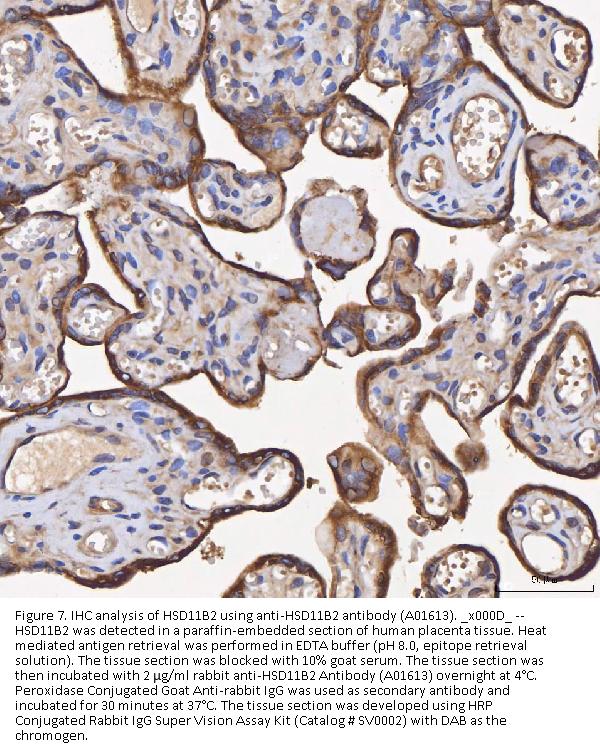

Immunohistochemistry(Paraffin-embedded Section), 2-5 μg/ml, Human

Boster Bio Anti-HSD11B2 Antibody Picoband® catalog # A01613. Tested in ELISA, Flow Cytometry, IF, IHC, WB applications. This antibody reacts with Human. The brand Picoband indicates this is a premium antibody that guarantees superior quality, high affinity, and strong signals with minimal background in Western blot applications. Only our best-performing antibodies are designated as Picoband, ensuring unmatched performance.